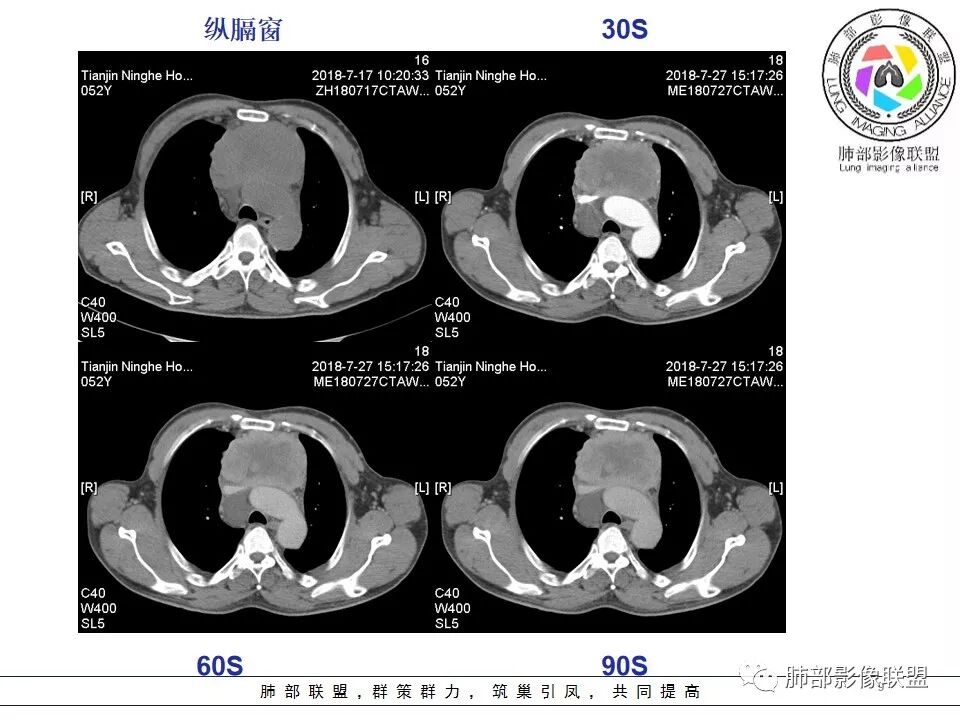

南边:强化就不用说了

大肿块,边缘不清,伴随肿大淋巴结,上腔静脉受侵犯——恶性

侵袭性胸腺瘤?胸腺癌?老年,钙化、肿大淋巴结,边缘侵犯、累及心包、侵犯上腔静脉——支持

b. ①纵隔脂肪间隙模糊、胸膜、心包侵犯、膈肌受累--见于高危胸腺瘤及胸腺癌,但是心包侵犯多见于B3胸腺瘤跟胸腺癌

②纵隔大血管侵犯、肺转移、膈神经麻痹、淋巴结转移及远处血行转移---多见于胸腺癌,B3胸腺瘤罕见

患者前纵隔囊实性肿块,常规疾病普考虑胸腺瘤、胸腺癌、生殖细胞肿瘤、淋巴瘤和神经内分泌肿瘤,其中神经内分泌肿瘤中最常见的是类癌,患者的年龄不支持生殖细胞瘤,具体分析如下:

1.  病灶内实质性钙化,提示AB型以上胸腺瘤、胸腺癌或类癌,其中微钙化往往提示高危型胸腺瘤跟胸腺癌、类癌,同时也排除了淋巴瘤(淋巴瘤不会有钙化);

2.  病灶呈分叶蔓延倾向,其内大片状囊变坏死,周围脂肪间隙模糊,提示高危型胸腺瘤或胸腺癌,但是类癌周围脂肪间隙往往很清晰;

3.  胸膜、心包侵犯,多提示高危型胸腺瘤中的B3型胸腺瘤、胸腺癌、类癌

4.  纵隔淋巴结肿大及纵隔大血管(上腔静脉)受侵犯,提示胸腺癌或类癌。